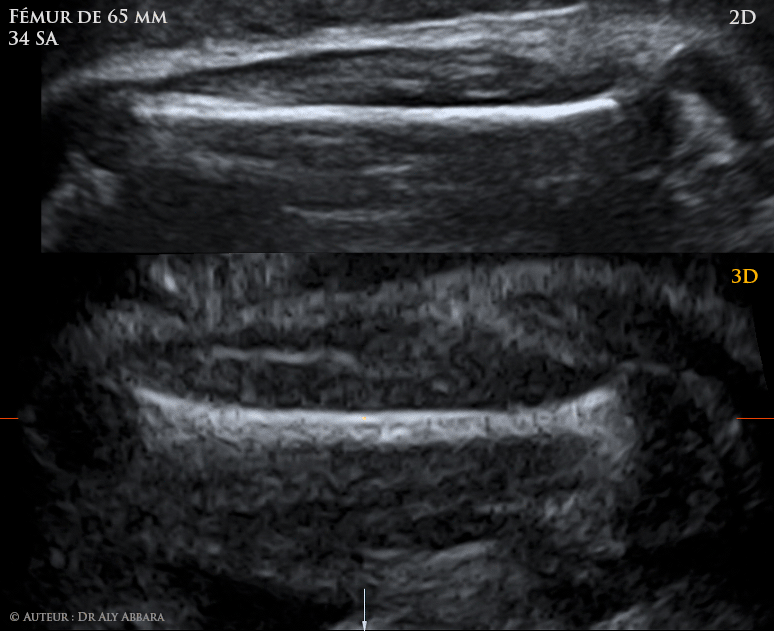

Fémure foetal et 3D et 2D - la partie mesurable

• Il doit être parfaitement horizontal sur l'écran (< 15 degrés) afin que, surtout au 3e trimestre, la largeur de la diaphyse n'apparaisse pas (observez la première image dans cet article).

• Les épiphyses ne doivent pas être prises dans ta mesure.

• Seule la diaphyse est mesurée, car il s'agit de la mesure de la seule diaphyse fémorale : si l'épiphyse distale est visible, l'artefact (lame plus ou moins fine ossifiée dans le prolongement de la diaphyse sur la surface de l'épiphyse) ne doit pas être inclus dans la mesure.